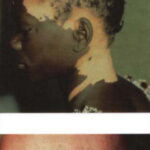

Patients with vitiligo present with one to several amelanotic macules that appear chalk- or milk-white in color. The lesions are usually well-demarcated, but the margins may be scalloped. They are accentuated on Wood's lamp examination. Lesions enlarge centrifugally at an unpredictable rate and can appear on any body site, including mucous membranes. However, initial lesions occur most frequently on the hands, forearms, feet, and face. When vitiligo occurs on the face, it often favors a perioral and periocular distribution.

Depending on ethnic color, vitiligo is more or less conspicuous .

Vitiligo may affect active melanocytes throughout the body, including pigment cells present in hair, the inner ear, and the retina. Poliosis (leukotrichia) occurs in many patients. Premature graying has been reported in vitiligo patients and in their close relatives. Auditory and visual disturbances are present in some patients. Aseptic meningitis may rarely result from destruction of leptomeningeal melanocytes.